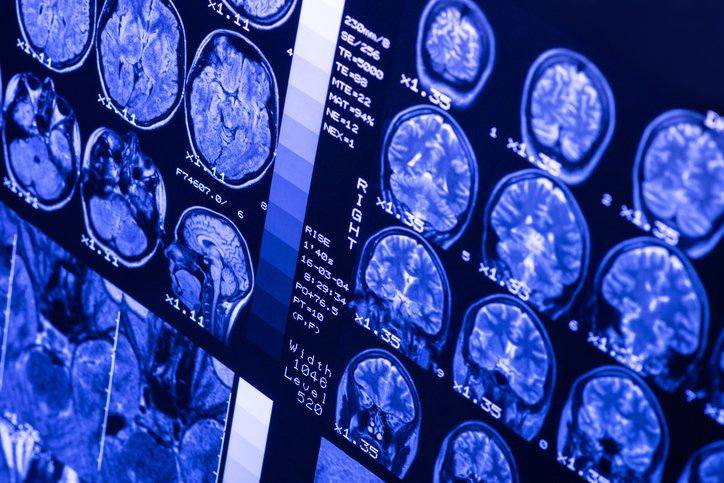

사진=게티이미지코리아. |